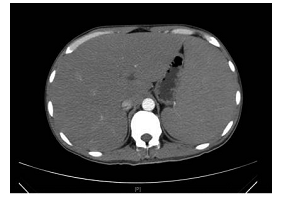

规培朋友看过来--核医学病例及解析(183号)

1010x864 - 275KB - PNG